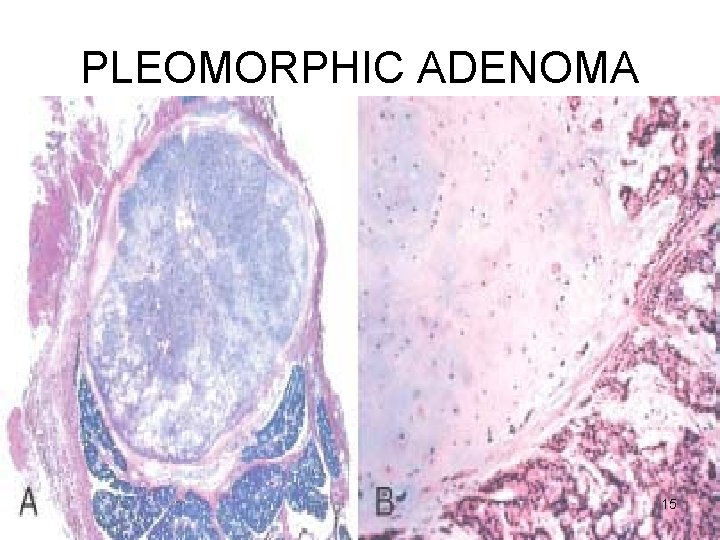

PLEOMORPHIC ADENOMA Gross • < 6 cms • Bosselated • Well-demarcated / encapsulated / tongue-like protrusions • Cut surface: gray-white / variegated / myxoid / bluish translucent (chondroid) 11

PLEOMORPHIC ADENOMA Microscopy • HETEROGENITY ! → PLEOMORPHIC • EPITHELIAL : epithelial & myoepithelial cells arranged in ducts, acini, irregular tubules, strands, sheets NO DYSPLASIA • MESENCHYMAL : myxoid, hyaline, chondroid, osseous 14